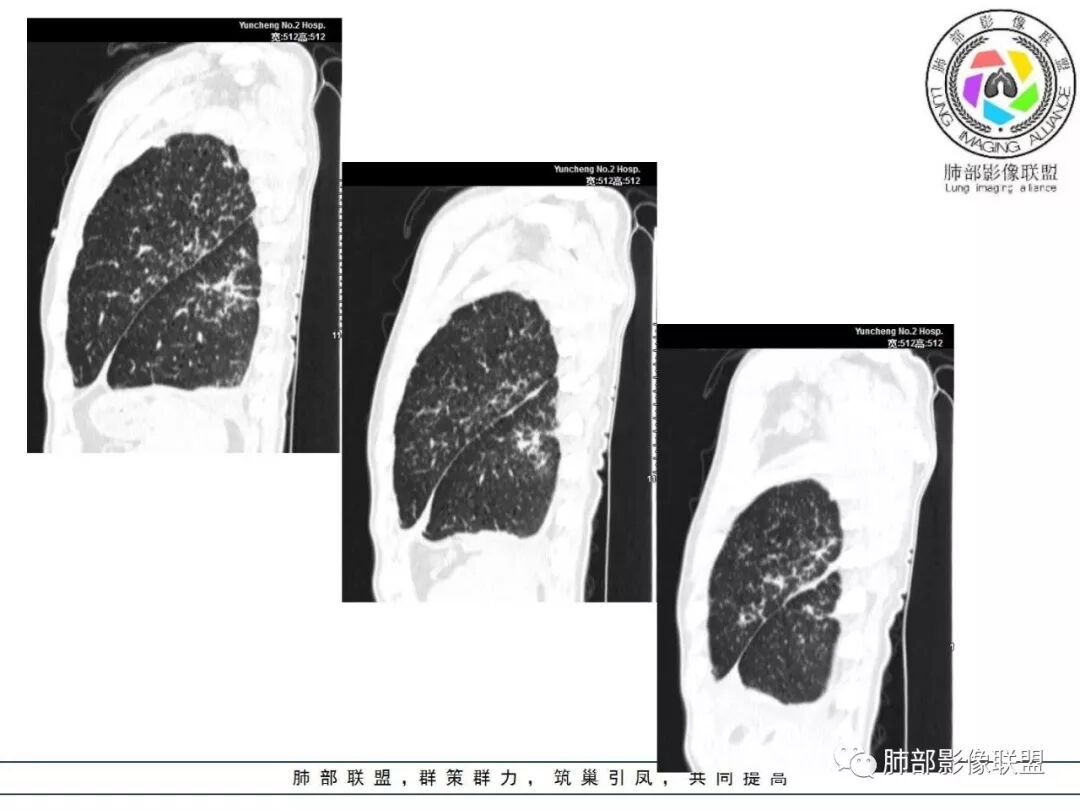

病变一般沿血管支气管束分布或小叶分布,一般上肺多于下肺(这与常见继发性肺结核分布相若)。

常会伴有其他继发性肺结核病灶,如斑片影、结节影,树芽征,新旧不等改变。

2. 肺气肿背景(小叶中心性肺气肿);双肺多发病灶整体沿血管支气管束及胸膜下分布,以上叶及下叶背段分布为主,有实变及GGO,边界清楚,有树芽,小叶间隔及中央间质增厚,叶间裂见到多发结节,部分支气管不规则牵拉扩张,提示病灶纤维化明显,结合临床病史,考虑病灶为间质性感染,肺门及纵隔内有钙化淋巴结,小叶间隔结节,考虑淋巴道增值性疾病可能,综合常规要怀疑间质性肺结核。

3.  该病例临床提示感染,有支气管扩张,提示纤维化,需要与感染后的OP鉴别,但是OP病灶常无结节感;间质性肺结核有时与不典型结节病鉴别也比较困难,结节病常以双肺门淋巴结增大为特征。临床上结核发病率较高。